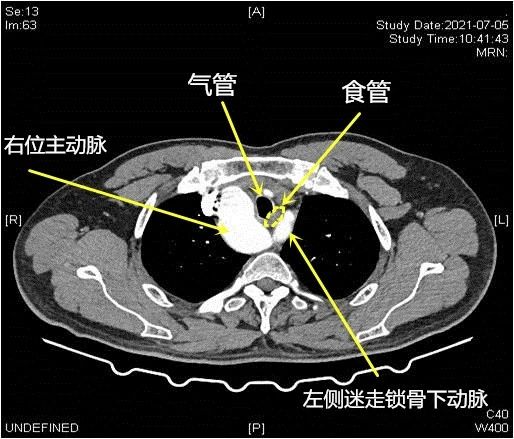

▲食管、异位主动脉弓及其上纵隔变异大血管关系示意图

他进一步解释说,目前主流的食管癌手术,都是通过右胸来游离食管,但由于老廖是右位主动脉弓,把食管全部推向左侧,右边则有主动脉弓的遮挡,所以只能从左侧进胸。这样一来,手术中医生就要面临更多的挑战。

首先上胸段食管的游离困难。在上纵隔,由于食管被左侧颈总动脉、锁骨下动脉和气管包绕,导致上胸段食管的游离非常困难。

最后,食管癌切除后,替代食管的管状胃如何上提至颈部并进行吻合,这也是医生要面临的新挑战。常规的食管癌手术,管状胃是经食管床上提至颈部并进行吻合,然而由于左迷走锁骨下动脉和气管之间的食管床间隙狭小,该患者无法按常规路径上提管状胃。